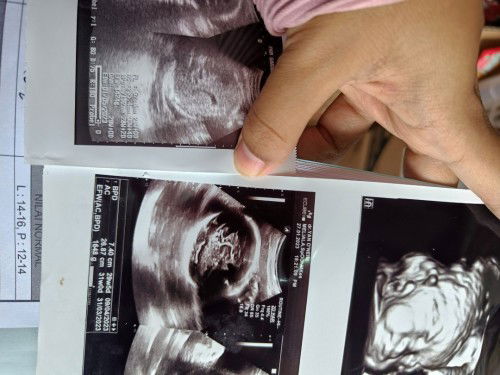

Perbedaan hasil USG puskesmas dan rumah sakit

Bund, ini yg sebelah kanan aku uSG di tgl 27januari, dan BB baby udah 1.6, usia kandungan juga udh masuk 29-30 Minggu. Tapi hari ini tgl 13feb keitung 2mingguan setelah USG ke dokter aku uSG lagi ke puskes sekalian cek HB, tapi usia kandunganku baru 29-30 week BB baby juga cuma 1.4. Aku khawatir bngt bund, soalnya hasil lab juga menyatakan protein urine saya positif, saya bingung apa ada kesalahan saat pemeriksaan, atau ada pengaruh ke baby gara2 protein saya positif Hb juga rendah🥺